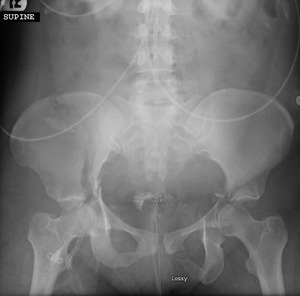

The patient was a 37-year-old female pedestrian struck by an automobile at an unknown speed, thrown into and struck by a second vehicle at an unknown speed, and subsequently brought to our Level 1 trauma center. The patient was initially unresponsive with declining mental status and required rapid sequence intubation in the trauma bay. She had obvious injuries on visual inspection including multiple superficial lacerations and abrasions, deformity to the right femur, shortened and externally rotated left leg, and a large open wound to the left foot. Initial standard trauma radiographs of the chest and pelvis were obtained. The single anterior-posterior (AP) chest film demonstrated several consecutive left segmental rib fractures with an associated pneumothorax. The AP pelvic radiograph showed a right iliac wing fracture, bilateral acetabulum fractures with left hip dislocation and femoral head medialization, right sacral fracture, and left inferior pubic ramus fracture (Figure 1). Physical examination demonstrated gross instability to right distal femur and left knee in coronal and sagittal planes, open and grossly unstable fracture to left midfoot. No pulses were palpable in the bilateral feet, but Doppler biphasic signals were audible at the right popliteal and posterior tibial arteries, as well as at the left popliteal and dorsalis pedis arteries.